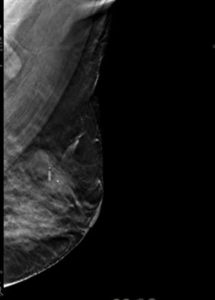

39yr old lady with history of lump in the left breast UIQ, No previous imaging done. No positive family history for CA Breast/Ovary. Pre-Menopausal Status.

Mammography- Fairly well circumscribed predominantly sold lesion in the left breast UIQ with partially obscured margins. No spiculations. No associated microcalcifications noted. Sonography: Well defined hypoechoiec lesion with smooth margins.

Low-grade Mucinous Carcinoma ER?PR- +ve HER-2 NEU -VE